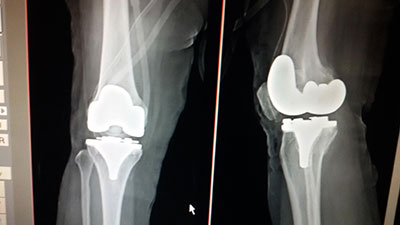

Case 8: Total Knee Replacement

Both knee osteoarthritis in a 62 years female.

Images

Both knee osteoarthritis

X-RAY 2

xray after both knee replaced